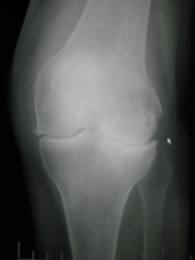

Osteoarthritis adalah kondisi yang mempengaruhi sendi dan merupakan jenis yang paling umum dari artritis di Inggris. Hal ini terutama terjadi pada lutut, pinggul, dan sendi kecil tangan, tapi hampir semua sendi dapat terpengaruh.

Professor Tim Spector, penulis senior makalah ini menambahkan: “Penelitian kami adalah studi pertama yang menggunakan metabolomik pendekatan untuk mengidentifikasi biomarker metabolik baru untuk osteoartritis. Kami berharap dengan penelitian lebih lanjut kedua rasio metabolit ini dapat diadopsi dalam praktek klinis, memungkinkan dokter mendiagnosa atau mengidentifikasi osteoarthritis yang sedang berkembang, sebelumnya Studi kami juga menunjukkan potensi besar klinis metabolomik dan kami berharap di masa depan dapat digunakan untuk memantau efektivitas perawatan. Pada saat ini kita tergantung pada roentgen – dan ketergantungan kita pada metode ini adalah suatu hambatan yang besar untuk pengembangan obat baru untuk osteoartritis. ”